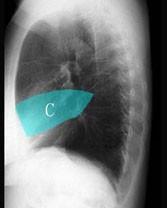

在图所示正常胸部X线影像图像上,该英文字母所代表的肺段为 ( )A、舌叶上段B、前段C、后段D、尖后段E、尖段

问题 在图所示正常胸部X线影像图像上,该英文字母所代表的肺段为 ( )

选项 A、舌叶上段 B、前段 C、后段 D、尖后段 E、尖段

答案 A